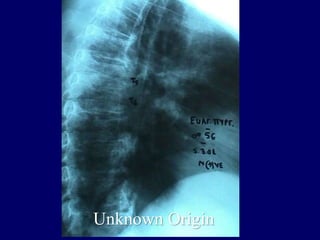

3rd case

EV. PY.

M 56 – Industrial labor

Symptoms

 Neurologic deficit

 Thoracic Pain

 Low fever

Laboratory

 Neutroph. ↑

 SR 45

Unknown Origin